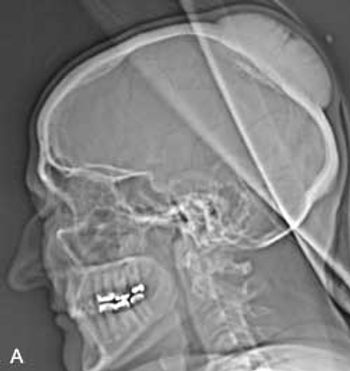

A 77-year-old woman was concerned about a "bump" on her head. The asymptomatic mass had been present for 4 years and had slowly enlarged.